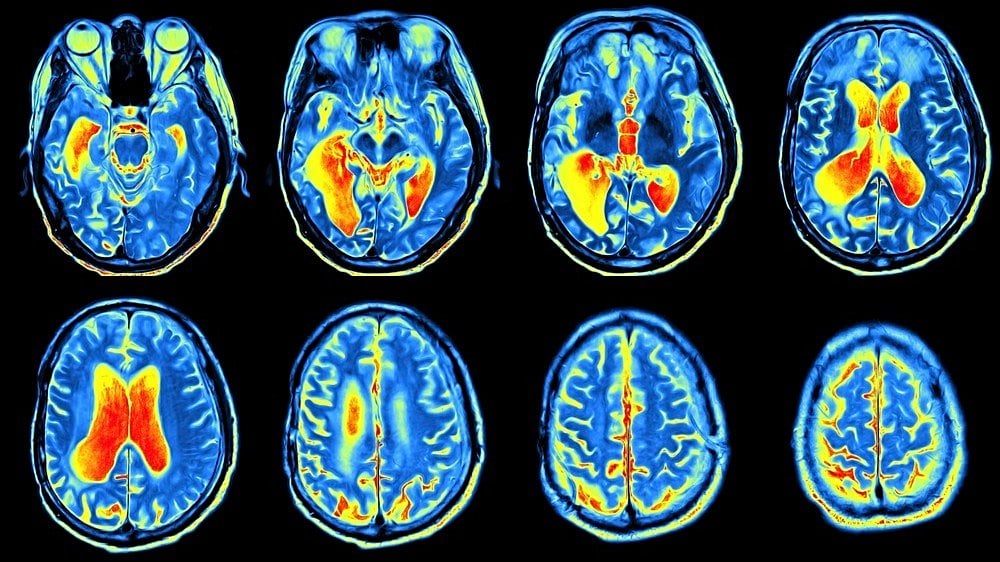

PET ve Diğer Görüntüleme Yöntemlerinin Karşılaştırması

PET taramaları, bir organ veya dokudaki metabolik değişimleri hücre düzeyinde gösterebilir. Bilgisayarlı tomografi (CT, veya Türkçe karşılığı BT) ya da manyetik rezonans görüntülemenin (MRI) sahip olmadığı bu özellik, hastalıkların genellikle hücresel düzeyde başlıyor olmasından dolayı önemlidir.

Bu sayede çoğu hastalığı erken evrede tespit edebilen PET taramaları, kompleks sistemik hastalıkların teşhis ve tedavisi için önem arz eder. CT ve MRI ise, hastalık ileriki aşamalarda organ veya dokuların yapısını bozmaya başladığında tespit yapabilir.

- CT taraması, özel X-ışınları kullanarak vücut içinin görüntüsünü oluşturur.

- MRI taraması ise manyetik alan ve radyo frekansı kullanarak bu işlemi gerçekleştirir.

Bu tarama yöntemlerinden birinin, PET taraması ile birlikte gerçekleştirilmesine görüntü birleştirme denir ve çoğu durumda, bir PET-CT veya PET-MRI taramasından geçmek mümkündür.

Bir bilgisayar, iki taramanın sonuçlarını birleştirerek daha fazla bilgi edinilebilen ve daha kesin teşhis yapmaya yarayan üç-boyutlu (3D) bir görüntü ortaya çıkartır.